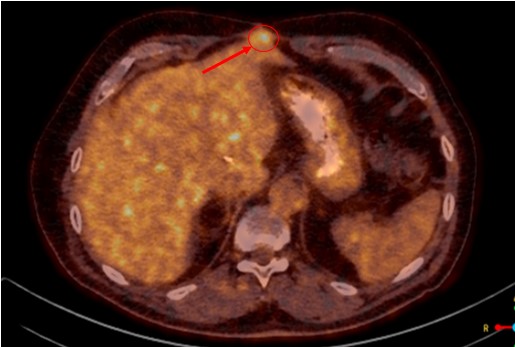

SABR meta pulmonis dex et hepatis, SB Radiochirurgia, 7.5.2022.

Rezultat – 13 mjeseci nakon RK

Potpuni nestanak tretirane lezije